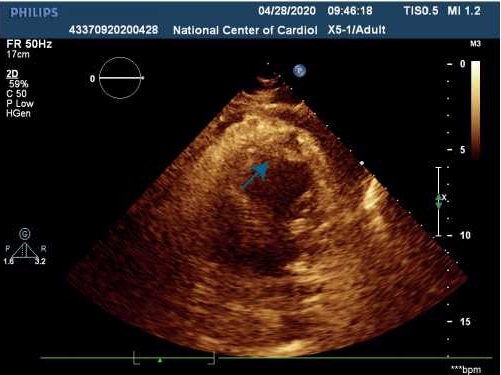

Несмотря на принимаемые меры лечения, состояние пациентки оставалось тяжелым, на фоне кардиогенного шока отмечались признаки острого почечного повреждения (скорость клубочковой фильтрации составила 17 мл/мин/1,73 м 2 ), острой энцефалопатии. По данным трансторакальной эхокардиографии (ЭхоКГ) сердца (табл. 1) на фоне акинеза среднего и апикального сегментов межжелудочковой перегородки, передней и боковой стенок левого желудочка (ЛЖ) с захватом верхушки ЛЖ, отмечалась сепарация листков перикарда в диастолу — 1,2 см за задней и боковой стенками ЛЖ, у верхушки — 0,8 см за счет наружного разрыва миокарда. Вся полость перикарда заполнена отложениями фибрина умеренной эхогенности. В области верхушки со стороны полости ЛЖ лоцировался дополнительный эхосигнал (пристеночный тромб) размером 2,7х1,6 см, под которым визуализировалось эхонегативное пространство размером 1,6х0,9 см (место разрыва миокарда) (рис. 4, 5). Кровоток через место разрыва миокарда не определялся.

Рис. 5. Трансторакальная ЭхоКГ пациентки Б.

Примечание: парастернальная позиция ЛЖ по короткой оси: полость перикарда заполнена отложениями фибрина умеренной эхогенности. В области верхушки ЛЖ лоцируется дополнительный эхосигнал (пристеночный тромб).

Сокращение: ЛЖ — левый желудочек.